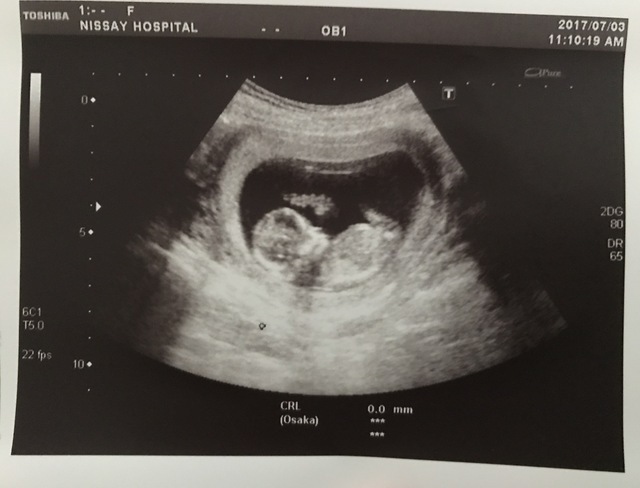

12週0日(12w0d・女の子)|yuki0255 さん(23歳)

エコー写真撮影時のエピソード:

初めの頃は、カシューナッツみたいで人間らしさもなかったのに、それでもそれがまたかわいくて次の検診が楽しみで毎日を過ごしていて、やっと人間らしくなって前よりも愛おしく思えました。

今でも寝る時は横を向いて寝るので、お腹の中と同じポーズだなぁと思いながら我が子を眺めてます。